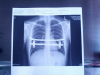

mal eben eine Rückmeldung zur Schmerztherapie. Es wurde ein

Röntgen Bild gemacht um auszuschließen das es kein

Pneumothorax ist. Hat sich, wie ich vermutet habe natürlich

nicht bestätig. Aber besser einmal mehr nach schauen als

gar nicht.